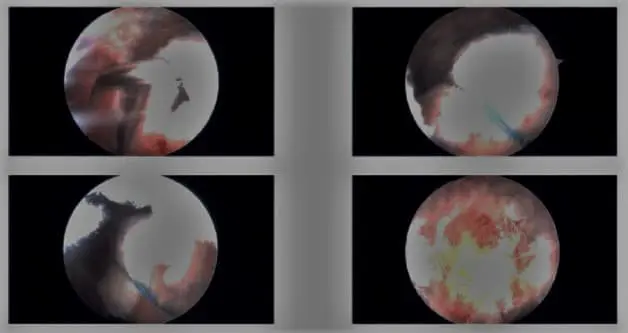

Intraoperative arthroscopic images.

A. A small incision is made in the shoulder, and a camera is inserted to visualize the joint. Instruments are used to treat the condition, such as repairing or removing damaged tissue.